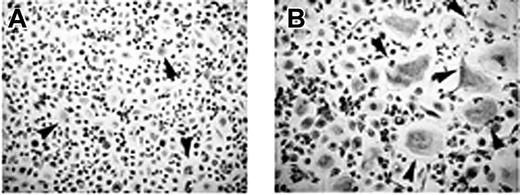

T cells mediate osteoclastogenesis in human MM PBMCs. Osteoclastogenesis occurred in T-cell–depleted MM PBMCs cultured in the absence (A) or in the presence (B) of M-CSF and RANKL. Small-sized OCs developed in the absence of M-CSF and RANKL (A), whereas exogenous cytokines triggered the formation of large-sized OCs (B). Multinucleated and TRAP+ cells were identified as OCs. The arrows point to the OCs (magnification × 200).

The unstimulated cultures of T-cell–depleted PBMCs from patients with MM with osteolysis resulted in the development of few small-sized OCs (OC average number/well = 10 ± 2) (Figure 2A). By contrast, the addition of M-CSF and RANKL to these cultures induced the formation of numerous large TRAP+ OCs (OC average number/well = 68 ± 5) (Figure 2B), like those observed in the presence of T cells (Figure 1Aii). In the T-cell–depleted and stromal cell-free BM cultures, OCs did not form (data not shown).